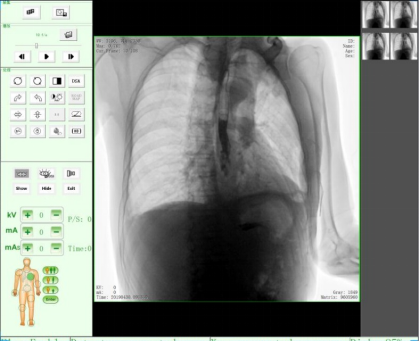

動態(tài)DR17*17英寸非晶硅動態(tài)平板探測器,透視像素達200萬,可實時顯示大幅面高清拍攝視野。適用于全身各部位攝影,包括常規(guī)攝影,如胸片、頸椎、腰椎、腹部、頭顱、四肢等,以及特殊攝影。

胸片